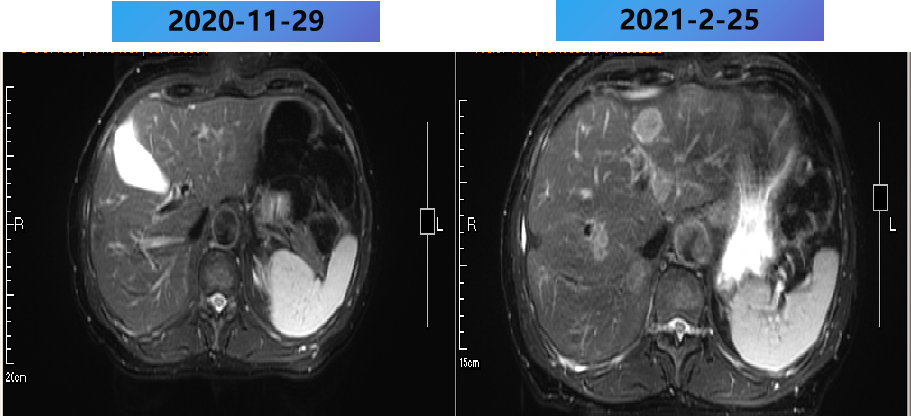

2021-2-20 (术后8m) 当地复查腹部MRI:肝脏多发转移瘤消融术后,较2021-1-5病变数目增多,体积增大。

2021-2-25至2021-7-15 更换方案为bev+伊立替康+雷替曲塞 9周期,部分病灶稳定(SD)。

2021-2-25至2021-7-25 更换方案为bev+伊立替康+雷替曲塞 9周期,部分病灶PD。

2021-2-25至2021-7-25 更换方案为bev+伊立替康+雷替曲塞 9周期,肺内病灶稳定(SD)。